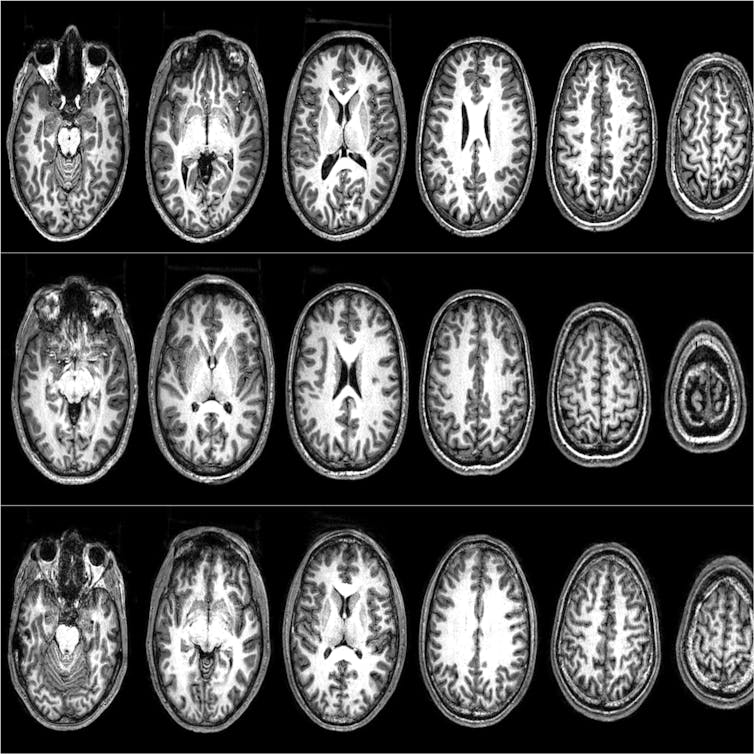

For our brain scans we used a tool called functional magnetic resonance imaging (fMRI) which records and identifies which areas of the brain are active during specific tasks. Our first fMRI study explored what could make non-sacred values become more like sacred values.

Unsurprisingly, participants rated higher willingness to fight and die for sacred rather than non-sacred values. Neurally, sacred values activated the left inferior frontal gyrus (IFG) – an area associated with rule processing and previously correlated with sacred values in American university students. But those who were excluded increased their willingness to fight and die for their non-sacred values, and the left IFG became activated even during non-sacred value processing.

In the first part of the study, they were scanned while rating their willingness to fight and die for their sacred and non-sacred values. These participants showed a different pattern of neural activity from the Moroccans in our first study, who exhibited the same patterns as US university students.

As the highly radicalized Pakistani men rated their sacred values, there was deactivation in a network that includes the dorsolateral prefrontal cortex (DLPFC), a part of the brain which is associated with deliberative reasoning and integrating cost-benefit calculations. When they rated a high willingness to fight and die for their values, we found increased activation in the ventromedial prefrontal cortex (vmPFC), a part of the brain that is associated with subjective valuation (how much value does this have for me?). In daily life, the DLPFC and vmPFC work in tandem when making decisions.

A follow-up analysis found that these two regions of the brain were highly connected when participants rated low willingness to fight and die – that is, subjective value was regulated by decision control mechanisms. But when they rated high willingness to fight and die, we found that these two regions were more disconnected. This suggests that, when someone is ready to kill and be killed in defence of an idea, they are no longer using decision control mechanisms typically involved in deliberative reasoning.

They essentially disengage this part of their brain. But, their willingness to fight and die lowers as their deliberative and subjective valuation regions reconnect. So what mechanisms bring people to lower their willingness to fight and die for a cause?

Despite this, we found that people lowered their willingness to fight and die for both sacred and non-sacred values to conform to the responses of their peers. This change was correlated with increased DLPFC activation in the brain. Their deliberative pathways were reopening.